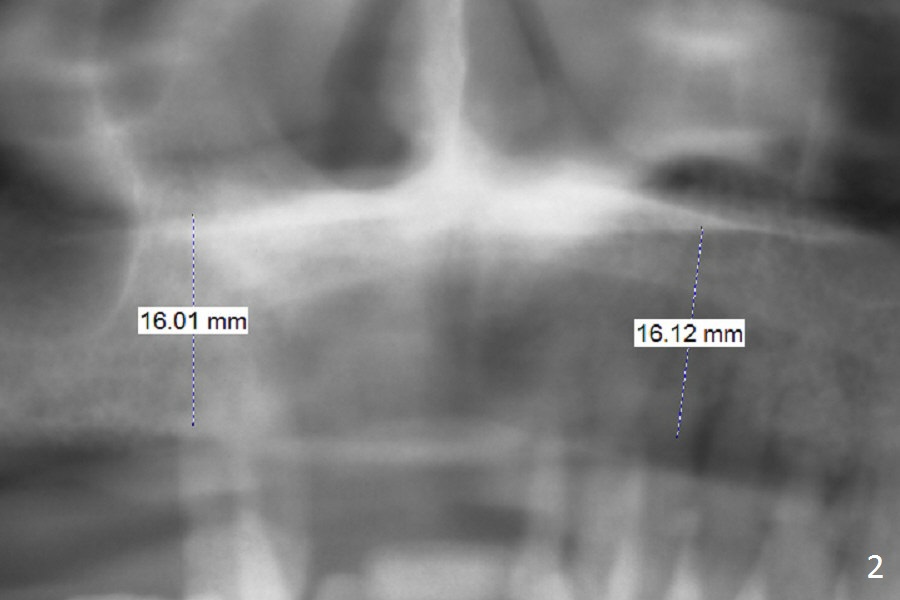

A 65-year-old woman has an upper partial denture and 3 mobile teeth (Fig.1 : #5,12,13). She wants to keep the RPD. The loose teeth are replaced by implants. There is enough bone height (Fig.2). Initial osteotomy depth will be 14 mm. Insert parallel pin(s) and take PA.